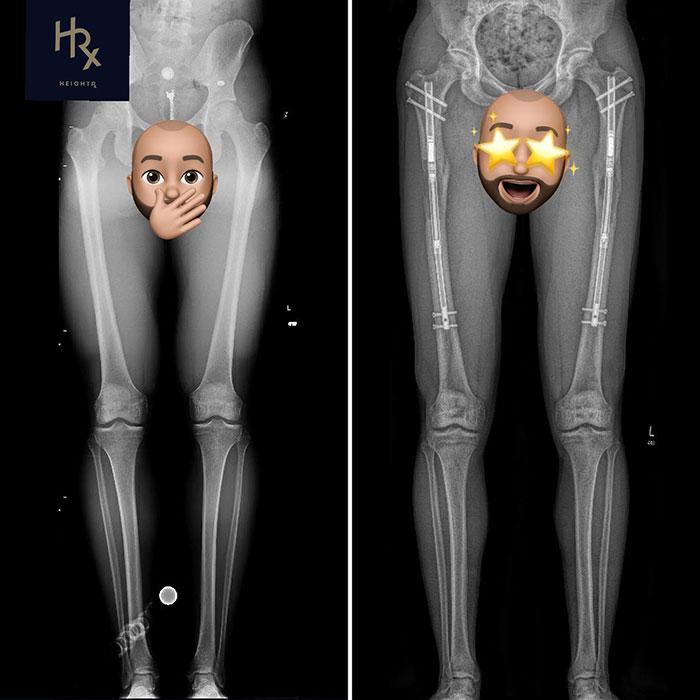

Theresia’s leg-lengthening journey involved multiple surgeries that spanned several years. The process began with an osteotomy, where surgeons cut her thigh and shin bones into two segments. Metal rods were then inserted to gradually separate the bone segments, allowing new bone tissue to form in the gap. Surgeons used two types of devices for this procedure:

Limb-lengthening surgery, while originally designed to treat conditions like skeletal dysplasia and bone deformities, has gained popularity for cosmetic purposes. The process involves two key phases:

- Osteotomy: The bone is cut into two segments.

- Bone Distraction: A limb-lengthening device gradually separates the bone segments, allowing new bone tissue to form in the gap.